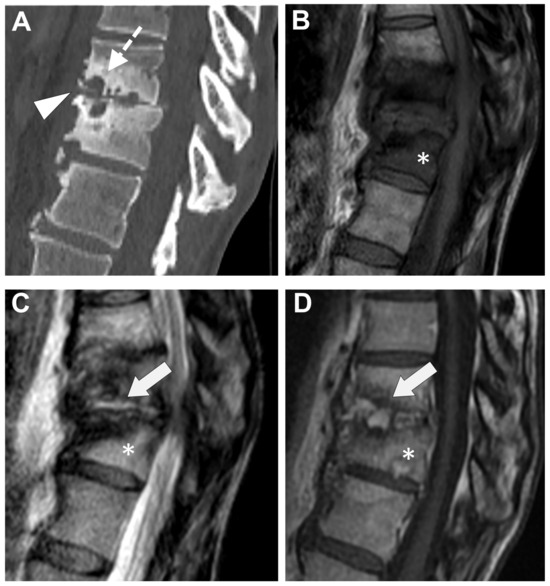

Figure 6. Tubercular spondylodiscitis. A 24-year-old man of Sudanese origin presented with thoracic and lumbar pain evolving for several months. An MRI was performed with (A) T2-weighted imaging (WI) and (B) contrast-enhanced (CE) T1-WI, as well as a CT-scan in bone kernel (C) and abdominal kernel after contrast medium injection (D,E). It demonstrates preserved disk but extensive sub ligamentous collections spreading along the anterior side of the thoracic and lumbar vertebral bodies (white arrowhead), but also along the posterior vertebral collateral ligament (white arrows) with large anterior and posterior erosions (black arrows). Please note the extensive collections spreading in the presacral space and along bilateral iliopsoas muscles without surrounding inflammation (white dashed arrows).